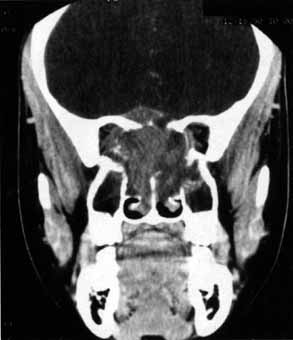

Anosmia caused by damage of cranial nerve I may be a helpful symptom of ethmoid or sphenoid sinus tumors invading the orbit (Fig. 20).44 Olfactory groove meningiomas and esthesioneuroblastomas may also present with anosmia prior to developing vision loss.45 Trauma that involves the orbit and is associated with anosmia should be considered a basilar skull fracture with potential for cerebrospinal fluid leak until proven otherwise (Fig. 21).

Fig. 20 A 13-year-old child presented with a 2-week history of sinusitis and anosmia. Her visual acuity decreased to to 20/400 1 day prior to admission. Computed tomography shows a large ethmoid tumor extending through the cribriform plate and optic canal. A rhabdomyosarcoma was diagnosed by biopsy.